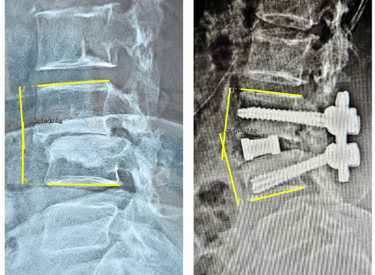

Degenerative Scoliosis Correction

Gentle corrections for lasting posture improvement.

Advanced Lateral Approaches - OLIF

Minimal invasive Spine Solution for maximum outcome.